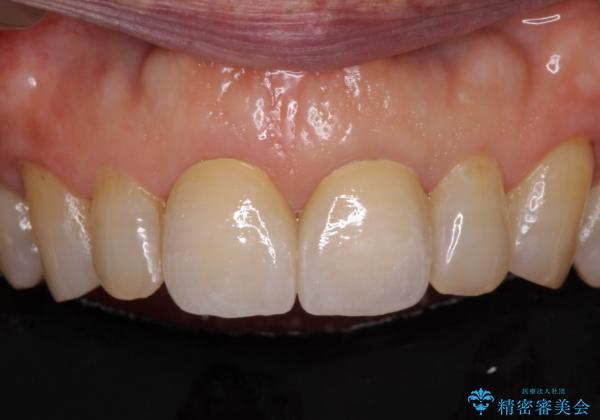

前歯の隙間をオールセラミッククラウンで自然に

- 前歯のすきっ歯を気にして来院された患者様です。

矯正かオールセラミックか、治療の選択がありましたが、ご年齢や色の濃い点を考慮してオールセラミッククラウンにて補綴することとしました。

折角なのできれいに仕上げたいとのことで、オーダーメイドタイプのクラウンを選択されました。色調を周りのご自身の歯と合わせることができるため、自然な仕上がりをご希望の方におすすめです。